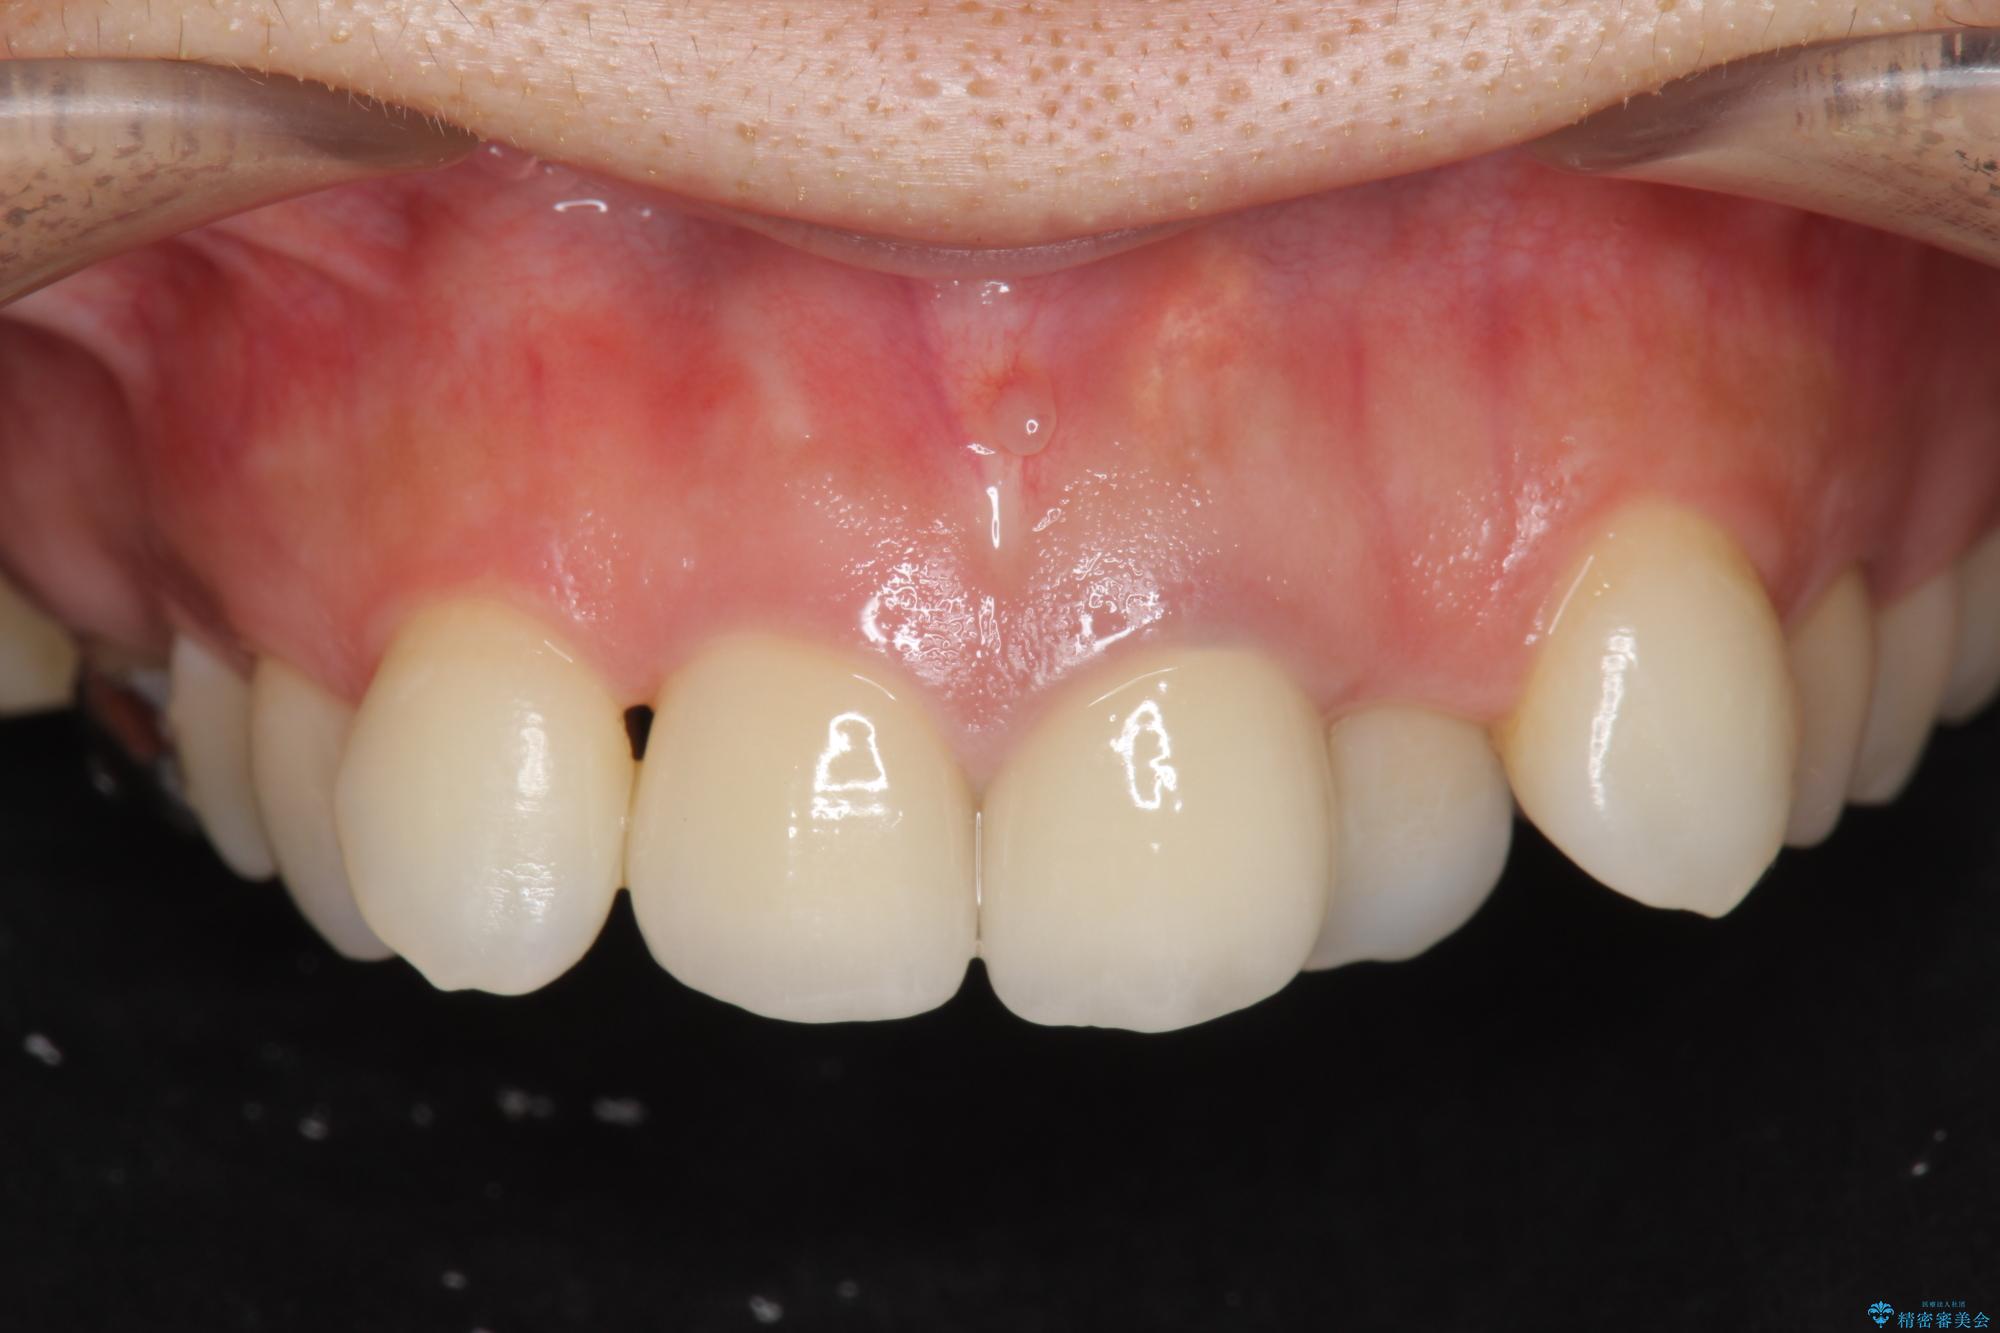

26.4万円(ジルコニアクラウン×2・仮歯×2)

レントゲン検査の結果、以前の根管治療の詰め物が突き出た状態でしたので、まず精密な再治療を行います。同時に、歯磨きがしにくく虫歯の原因になっている右上側切歯を抜歯し、その後、セラミック治療で全体を美しく修復する計画です。

歯磨きがしにくい歯を抜歯することで、今後の虫歯の再発を防ぐ治療計画としました。